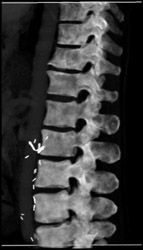

Diagnosis

Hip Deformity